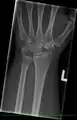

Left hand x-ray post proximal row carpectomy

X-Ray on Left Hand Post-Proximal Row Carpectomy, in Traction.

X-Ray on Left Hand Post-Proximal Row Carpectomy.